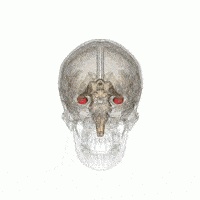

脑干及小脑(The Brain Stem and Cerebellum)

这是我们的大脑最古老的部分:

延髓(The medulla oblongata)

延髓真的只是让你不会死。它控制非自主的事情,比如你的心脏速率、呼吸和血压。

当它认为你中毒了,就会让你呕吐。

脑桥(The pons)

脑桥的工作是,做点这个,做点那个。它涉及吞咽,膀胱控制,面部表情,咀嚼,唾液,眼泪等等。

中脑(The midbrain)

中脑与视觉,听觉,动作控制,警觉性,体温控制有关,还有一堆其他的事情。大脑被分为了前脑、中脑和后脑。

小脑(The cerebellum)

这个看起来像你大脑阴囊的东西是你的小脑,它使人保持平衡、协调和正常移动。